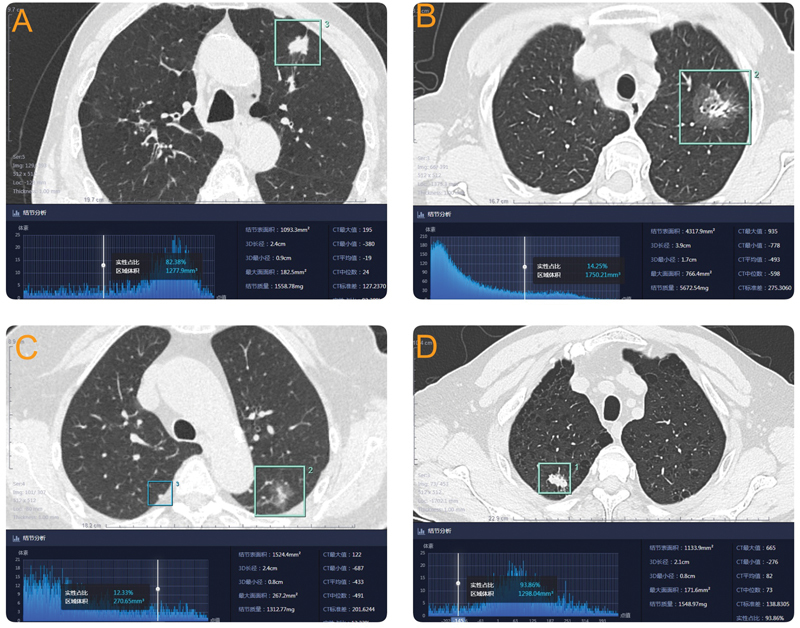

Methods: We analyzed the relationships between CT quantitative parameters (including three-dimensional parameters) and pathological grade and lymph node metastasis in cT1-stage lung adenocarcinoma patients of our center between January 2015 and December 2023.

Results: A total of 343 patients were included, of which there were 233 males and 110 females, aged 61.8 ± 9.4 (30-82) years. The area under the receiver operating characteristic (ROC) curve for predicting the pathological grade of lung adenocarcinoma using the consolidation-tumor ratio (CTR) and the solid volume ratio (SVR) were 0.761 and 0.777, respectively. The areas under the ROC curves (AUCs) for predicting lymph node metastasis were 0.804 and 0.873, respectively. Multivariate logistic regression analysis suggested that the SVR was an independent predictor of highly malignant lung adenocarcinoma pathology, while the SVR and pathological grade were independent predictors of lymph node metastasis. The sensitivity of predicting the pathological grading of lung adenocarcinoma based on SVR >5% was 97.2%, with a negative predictive value of 96%. The sensitivity of predicting lymph node metastasis based on SVR >47.1% was 97.3%, and the negative predictive value was 99.5%.

Conclusion: The SVR has greater diagnostic value than the CTR in the preoperative prediction of pathologic grade and lymph node metastasis in stage cT1-stage lung adenocarcinoma patients, and the SVR may replace the diameter and CTR as better criteria for guiding surgical implementation.